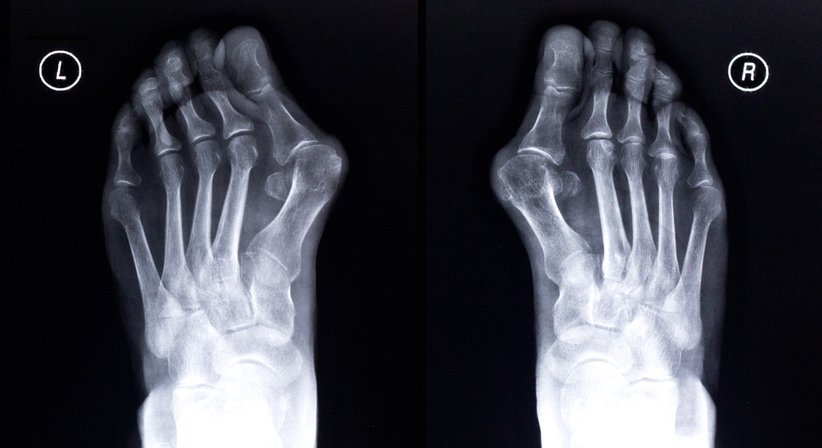

Der Hallux valgus stellt die häufigste Deformität des Vorfußes und der Zehen dar. Von einem Hallux valgus sind in erster Linie Frauen betroffen. Meist führen eine genetische Veranlagung sowie das Tragen von zugespitzten, engen Schuhen zu dieser Fehlstellung im Großzehengrundgelenk.

Einem Hallux valgus geht häufig ein Spreizfuß voraus. Die anfänglichen Beschwerden stellen oftmals ein rein optisches, kosmetisches Problem dar. Schreitet die Fehlstellung jedoch voran, kann es zu starken lokalen Schmerzen kommen. Zudem können Schwielen und Hühneraugen entstehen.

Ein Hallux valgus muss nicht sofort operiert werden. Anfangs können die Beschwerden durch das Tragen eines geeigneten Schuhwerkes, spezielle orthopädische Einlagen, eine gezielte Physiotherapie oder Schienen gelindert werden.

Bei erhöhtem Leidensdruck und deutlicher Fehlstellung ist jedoch die operative Korrektur indiziert. Die Operationsmethode richtet sich dabei nach dem Grad der Fehlstellung.